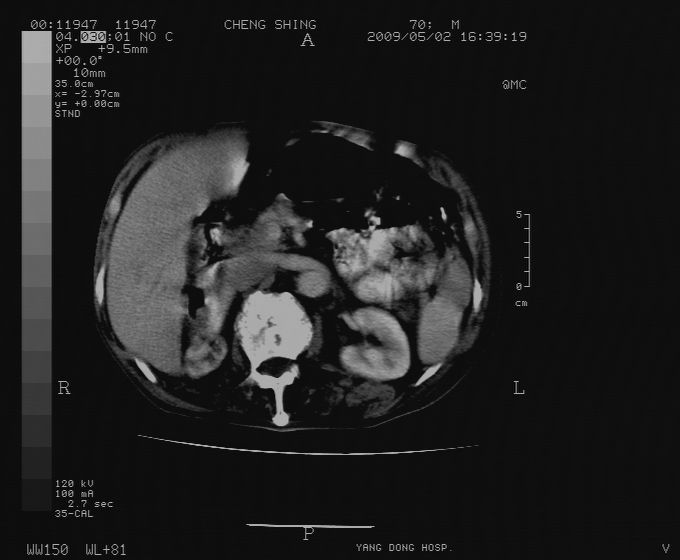

标题: CT19743:男70岁,肺部疾病入院,B超发现肝右叶占位,CT [打印本页]

标题: CT19743:男70岁,肺部疾病入院,B超发现肝右叶占位,CT

肝表面塌陷,病灶周围有子灶,前面较大子灶强化符合肝癌表现,考虑肝癌肝转移可能性大.

1.考虑肝癌肝转移

2.两侧胸水,左下肺不张!

1)考虑肝癌并肝内转移。2)少量腹水。3)双侧胸腔积液。

1)考虑肝癌并肝内转移。2)少量腹水及双侧胸腔积液。3)椎体退变。